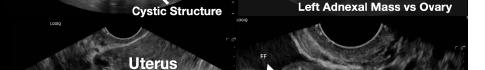

Her laboratory studies were notable for a hemoglobin of 11.9 grams per deciliter (g/dL) (reference range: 11.6-15 g/dL) and a normal white blood cell count of 8.4 thousand per cubic milliliter (k/μL) (reference range: 5-10 k/μL). Her lipase and liver function tests were within normal limits. Her human chorionic gonadotropin (hCG) had tripled from 6,253 milli-international units per milliliter (mIU/mL) (reference range: ≤2 mIU/mL) from her prior presentation to 18,038 mIU/mL. Transvaginal ultrasound showed a possible ectopic pregnancy adjacent to the right ovary and no intrauterine pregnancy (Image 1).

The patient declined medical abortion and was taken to the operating room for a right salpingectomy. On her initial presentation 11 days prior, the patient’s preoperative ultrasound had shown a complex focus of the left ovary with a hyperechoic thick rim suggestive of ectopic pregnancy and probable right-sided corpus luteal and anechoic cysts (Image 2, Image 3). No evidence of right ectopic pregnancy was documented intraoperatively during the patient’s initial salpingectomy. Pathology findings from the initial left- and subsequent right-sided procedures showed immature chorionic villi, congestion, and hemorrhage consistent with a tubal

Image 1. This image shows the patient’s ultrasound findings 11 days after her initial diagnosis of a left tubal pregnancy. The image on the left shows the right adnexa with an arrow pointing to a rounded cystic structure with a peripheral soft tissue component, blood flow, and free fluid. The image on the right shows the left ovary with two arrows pointing to a moderate amount of free fluid in the left adnexa. Image 2. This image shows the patient’s initial ultrasound findings. The image on the right shows two arrows pointing to the left adnexa with a complex focus measuring 2.5 x 2.6 x 2.6 centimeters (cm) with a cystic focus of 0.5 cm within it and a hyperechoic thick rim. The image on the left shows the right adnexa with arrows pointing to a small, probable 0.8 cm corpus luteal cyst and an anechoic cyst measuring 1.6 cm.

Image 3. This image shows both of the patient’s ultrasound findings as described above for ease of comparison. The upper panel is from the initial encounter and the lower panel is from the patient’s encounter 11 days later.